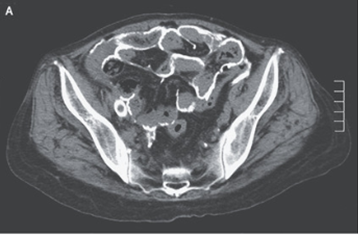

67歳男性。 約1か月前から呼吸困難、下痢が出現し、昨日から腹痛が出現したため外来を受診した。 身体所見では頚静脈怒張、左胸骨下縁の全収縮期雑音、びまん性喘鳴、…